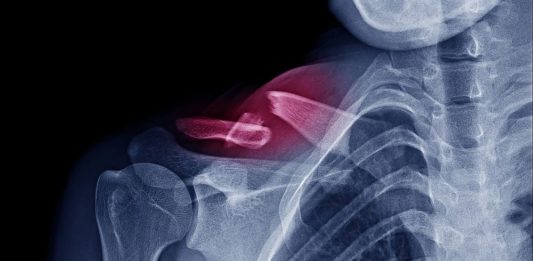

Ottimizzazione della salute ossea in chirurgia ortopedica

Quanto รจ importante una corretta valutazione osteometabolica del paziente candidato a chirurgia protesica? Prendendo spunto dallo studio “Bone Health Optimization in Orthopaedic Surgery” Gregorio Guabello, endocrinologo, e Federico Valli, chirurgo ortopedico, rispondono